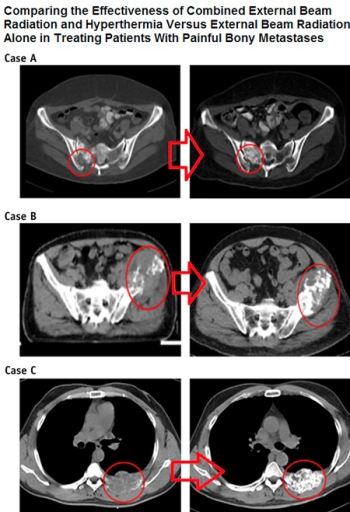

Yapılan bilimsel araştırmada, kemik metastazı olanlarda kanser kitlesinin tamamen ortadan kaldırılma oranları sadece radyoterapi verilmesiyle % 7 iken, radyoterapi yanıan derin doku RF hipertermi verilmesiyle % 38’ e çıkarılmaktadır. Ortalama ağrının olmadığı süre sadece radyoterapi alan hastalarda 55 gün iken, radyoterapiye derin doku RF hipertermi eklenmesiyle çok daha uzun süre ağrı olmadığı saptanmıştır.

Sonuç olarak ağrılı kemik metastazı olan hastalarda radyoterapinin yanına derin doku RF hipertermi eklenmesinin gerek ağrı kontrol süresini gerekse kemikteki kanser kitlesinin tamamen yok edilme şansını belirgin arttırmakta, hastalara daha iyi bir yaşam sunmaktadır.

Chi MS, Yang KL, Chang YC, Ko HL, Lin YH, Huang SC, Huang YY, Liao KW, Kondo M, Chi KH. Comparing the Effectiveness of Combined External Beam Radiation and Hyperthermia Versus External Beam Radiation Alone in Treating Patients With Painful Bony Metastases: A Phase 3 Prospective, Randomized, Controlled Trial. Int J Radiat Oncol Biol Phys. 2018 Jan 1;100(1):78-87.